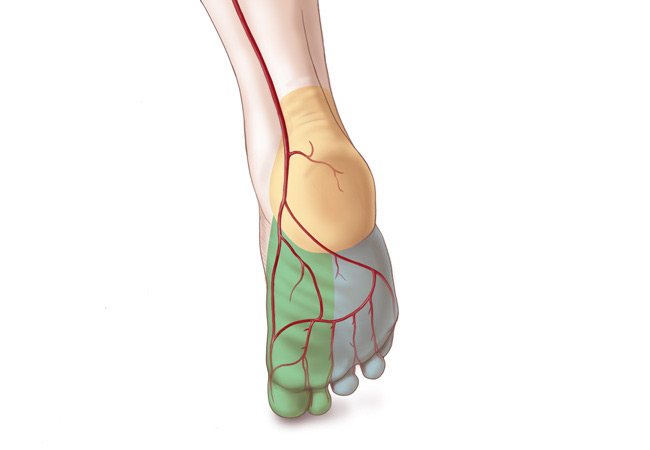

Increasing Circulation in the Lower Limb

The action of foot impulse technology (FIT) in reducing the risk of deep vein thrombosis (DVT) is well established. We hypothesized that intraoperative use of F......